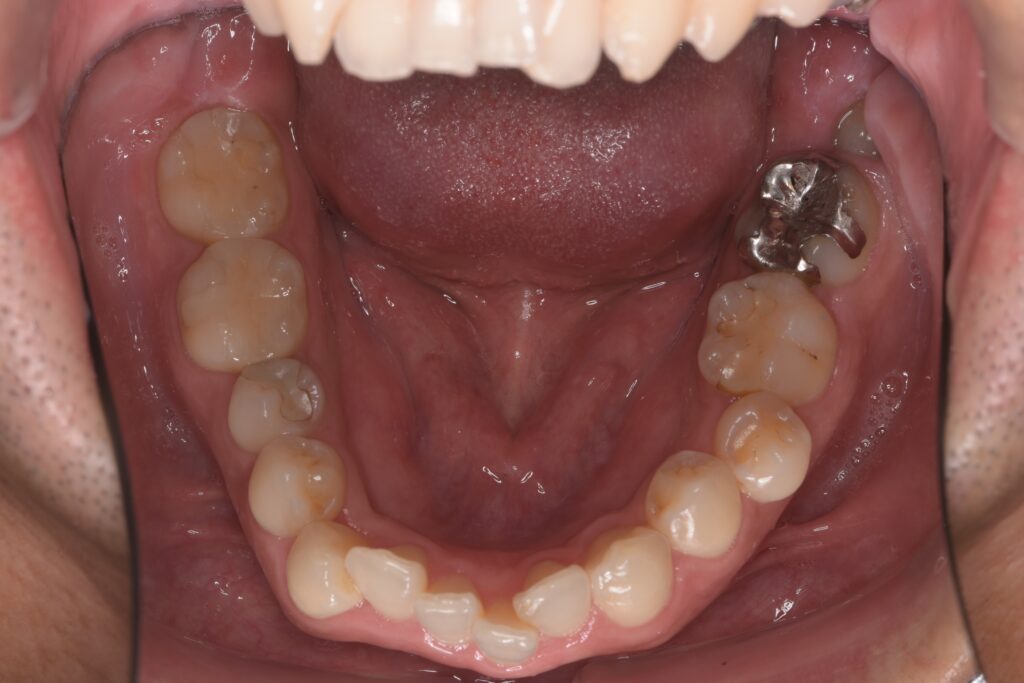

以下は症例写真です。

長年使用していた金属の詰め物を、生体親和性の高いセラミック素材に置き換えました。

天然歯のような透明感が生まれ、金属アレルギーの不安も解消されています。

<術前の写真>